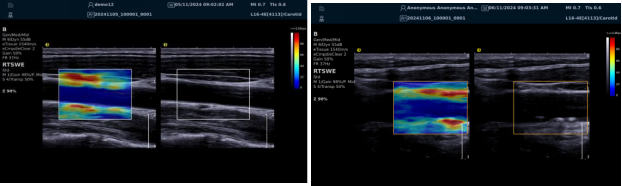

(一)RTSWE 实时剪切波弹性成像技术

RTSWE 技术源于对剪切波的创新研究,通过 MultiPush?超声触诊技术产生振动生成剪切波,OmniSound?平台提升帧频捕获信息并测量杨氏模量。其优势突出:

? 可视化,对颈动脉内膜和斑块实时弹性成像,彩色编码显示硬度,便于医生区分斑块类型。

? 定量测量方面,分析结果以kPa或m/s为单位测量颈动脉相关部位杨氏模量,毫米级分辨率显示微小病变,提供 20 余种参数综合评估斑块稳定性和血管硬化。因测量取样范围可极度小甚至对于颈动脉内中膜硬度可定量测量,引发不同视角评价极早期动脉硬化评估,实属科研利器。

? 采用马赫圆锥脉冲激励技术,无需按压,减少检查者影响,帧频高、操作简便、耗时短。

RTSWE 是全球唯一的实时全幅全定量剪切波弹性成像系统,OmniSound?平台采集与显示帧频国际领先,对颈动脉结构定量分析和脑卒中早期预防意义重大。